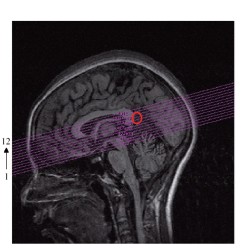

一九九八年,我們也用功能性磁造影(functional magnetic imaging,簡稱fMRI)技術測量了高橋小姐手指識字時大腦各部位的活動情形(如一○四頁圖2-15所示),並將大腦切割成十二條細長紫色線分隔的區間,包括視丘、松果體、胼胝體等部位。

圖2-15 手指識字時,用fMRI測量大腦各部位活動情形

紅色部位是開天眼前後信號變化較大的部位。從第7張腦顯影片可看到,左腦聽覺部位有變化,第8張起,腦中央部位一些區域有很大的變化。

高橋一手操控按鈕,開天眼時按一下作為信號,幫助分析數據。

如右圖2-15下方顯影圖所示,上排是第五、六、七、八的四片區域;下排是第九、十、十一、十二的四片區域,以及開天眼前後信號變化圖,紅色部位是較大的變化。很明顯的是,從第七張左腦聽覺部位有變化,第八張起中央部位一些區域有很大的變化。

下圖2-16中,大腦藍色區塊內顯示的是第八片紅色區域實際信號的變化圖,右圖中的橘色是高橋舞小姐開天眼時按下的信號,總共開了兩次天眼,縱軸是fMRI信號在天眼打開時變化的百分比。

圖2-16 大腦藍色區塊內,開天眼前後的FMRI信號變化百分比

圖表中藍色區間為頭部稍微移動的區間,但與第一次開天眼時間無關。第二次開天眼時信號變化達到140%。

第二次開天眼時,她信號變化竟然達到百分之一百四十,遠高於一般正常信號變化百分之一到三的五十倍。第一次測量時,所有專家沒有人相信這個數據,都認為頭有動。但是經進一步分析發現她頭稍微移動的時間並非第二次開天眼的時間,如藍色區間顯示。後來第二次作實驗時,信號反應還是一樣巨大,才說服大家這是真的信號。一○四頁圖2-15第九、十片腦區雖然信號變化較小,但是還是比一般信號要大得多,所以我們初步判定天眼開的部位是在下圖2-17紅圈的位置,很接近大腦中後扣帶皮層(posterior cingulate cortex,簡稱PCC)部位。

圖2-17 開天眼時,fMRI信號反應最強區域

紅圈位置,為開天眼時的反應部位,似乎很接近大腦中的後扣帶皮層。